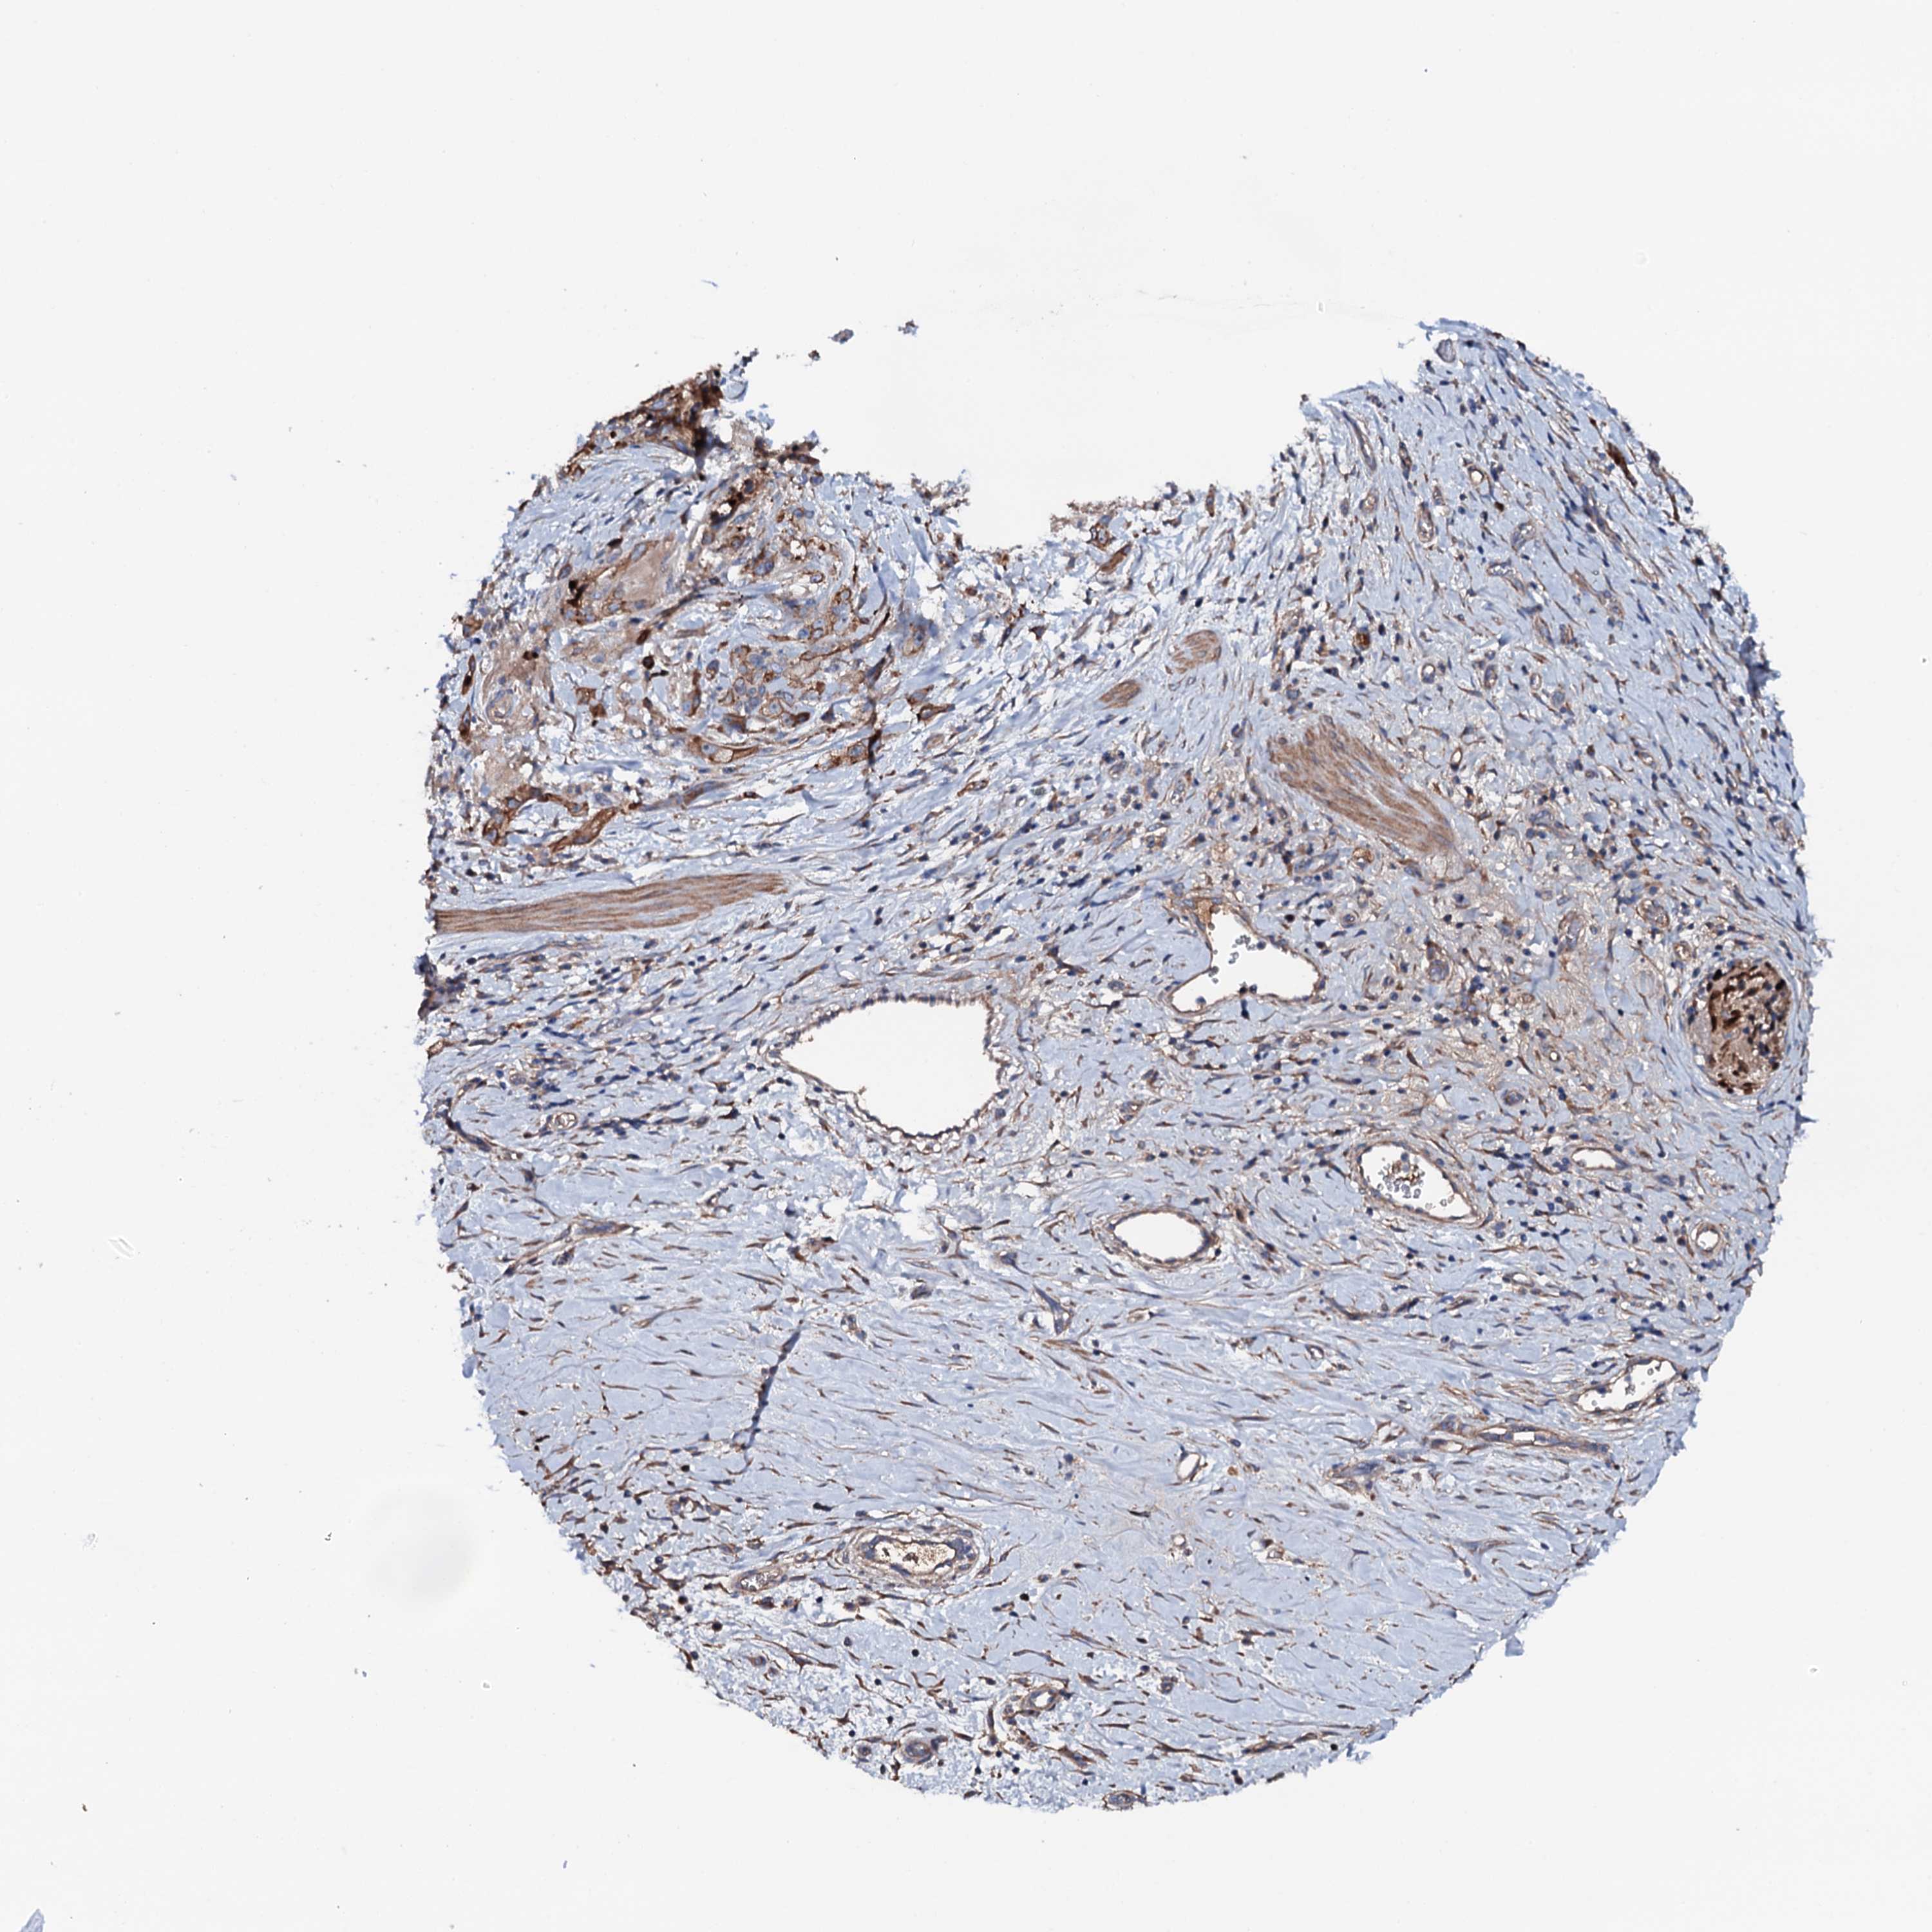

STOMACH CANCER - Protein expressioni

A mouse-over function shows sample information and annotation data. Click on an image to view it in a full screen mode. Samples can be filtered based on level of antibody staining by selecting one or several of the following categories: high, medium, low and not detected. The assay and annotation is described here.

Note that samples used for immunohistochemistry by the Human Protein Atlas do not correspond to samples in the TCGA dataset.

Antibody stainingi

Antibody staining in the annotated cell types in the current human tissue is reported as not detected, low, medium, or high, based on conventional immunohistochemistry profiling in selected tissues. This score is based on the combination of the staining intensity and fraction of stained cells.

Each image is clickable and will lead to virtual microscopy that enables deeper exploration of all samples and also displays staining intensity scores, fraction scores and subcellular localization as well as patient and tissue information for each sample.

Antibody HPA020873

Antibody HPA040413

Staining

High

Medium

Low

Not detected

Intensity

Strong

Moderate

Weak

Negative

Quantity

>75%

75%-25%

<25%

None

Location

Nuclear

Cytoplasmic/membranous

Cytoplasmic/membranous,nuclear

Adenocarcinoma, NOS

Adenocarcinoma, High grade